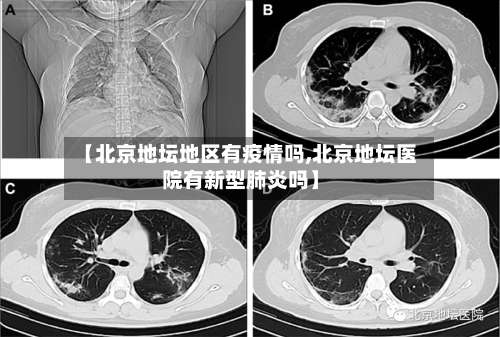

〖壹〗 、北京地坛医院一个确诊妈妈诞下新生儿,这个新生儿她并没有患有新冠 ,病毒经过接生之后将这个小孩子放在了封闭的一个区域内,也就让医护人员每天去检查他的身体以及帮他做一些咽拭子,在隔离了14天之后,发现证明孩子状况良好 ,没有患有新冠病毒。

〖贰〗、北京有一位即将生产的孕妇,而且这名孕妇是新冠病毒感染者,4月29日这名孕妇作为确诊病例转到了北京地坛医院 ,孕妇已经妊娠39周五天,随时都有可能会分娩,这名患者入院后引起了院内的高度关注 ,地坛医院的专家和市级专家一起制定了分娩方案 。